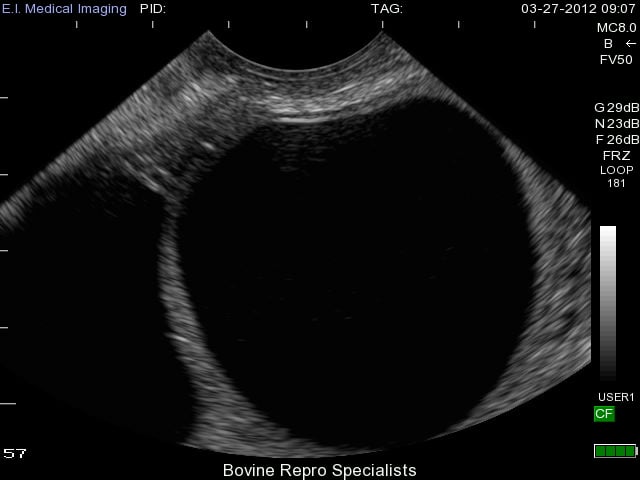

Development of follicular cysts in cows occurs when a follicle reaches the ovulatory size (about 17 to 19 mm), but fails to ovulate leaving a large persistent follicular structure on the ovary. A single follicular cyst or multiple cysts can form on the ovary (s). Length of time for the anovular follicle to persist on the ovary before it’s considered a follicular cyst is usually at least 10 days. There are various classifications of a “true follicular cyst”, but a classic identifying feature is a follicular structure on the ovary that is at least 25 mm in size in the absence of any corpus luteum. The appearance of follicular cysts is clear using ultrasound with the large cystic structure having a very thin outer wall with black fluid extending to its outer edges as shown in the image below.

As you can see, diagnosis of this type of cyst is clear with use of an ultrasound, and the presence of a second follicular cyst is evident on the left side of the ovary as well. Rupture of these cysts is quite easy from rectal palpation, which can traumatize the ovary leading to hemorrhaging, and possible adhesion formation on the ovary. The less invasive approach of using an ultrasound can reduce the chances of rupturing follicular cysts, and also is extremely effective to determine whether the cyst is active or benign. Palpating any other structure on an ovary is extremely difficult when a cyst is present, so many times an active corpus luteum is not found on the ovary along with the cyst. An example of this is shown below where the cyst is very prominent on the left side of the ovary, but can be classified as benign due to the corpus luteum sitting to the right of it.